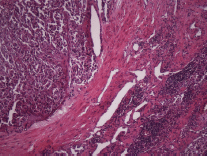

The subject is a 13-year-old female patient with a history of arterial hypertension, tachycardia, and cardiomegaly. In the clinical evaluation a palpable lump was found in the hypogastrium. Full laboratory tests were requested and the following relevant data were found: adrenaline and noradrenaline elevated in blood and urine. An ultrasound was carried out revealing an ovoid, heterogeneous solid mass of 4.4 × 3 cm in contact with the vagina and below the uterus, causing an effect of mass on the bladder. In order to determine the nature, characteristics, location, and relationships of this mass, magnetic resonance imaging (MRI) was requested and this reported an image of 4 × 6 × 4 cm, located in the retrovesical and right vaginal parauterine region in contact with the posteroinferior wall of the bladder, which it deforms (Figure 1). It was decided to perform a surgical biopsy of the lesion, obtaining the following anatomopathological results: paraganglioma. To assess functionality, the existence of lesions in other locations and the presence of metastases, a metamyodobenzylguanidine (MIBG) scan was requested, which was negative for neuroendocrine tumour metastasis. It was decided to perform surgical resection prior to pharmacological treatment. A laparotomy was performed, revealing a tumour in the retrovesical, parauterine, and right paravaginal region in contact with the vaginal vault and lower back part of the wall of the bladder. The lesion was dissected and resected respecting the vagina, uterus, and bladder (Figure 2). Coinciding with the surgical manipulation of the lesion, the patient presented fluctuation of arterial pressure that required pharmacological management. The anatomopathological study of both the biopsy and the resection revealed a proliferation of neoplastic cells that were predominantly present in solid nests separated by fibroconnective vascular stroma. The cells showed eosinophilic cytoplasm and mild nuclear pleomorphism (Figures 4 and 5). Immunostaining techniques were performed for chromogranin A and synaptophysin, both markers being positive (Figures 6 and 7). With these findings, the diagnosis of extra-adrenal pelvic paraganglioma was reached. The patient evolved for three years with local recurrences and metastases in intrapelvic lymph nodes due to the neoplasia described. These results were obtained due to the studies of positron emission tomography that revealed three pelvic hypermetabolic nodules (right side: 14.2 mm, left side: 14, 9 mm and 10.3 mm), with a hypermetabolic focus on the floor of the pelvis relative to the vagina, to the right of the midline, adjacent to the metallic suture clip (Figures 3 and 8).

Figure 4. Microscopy. Haematoxylin and eosin. 20x.

Figure 5. Microscopy. Haematoxylin and eosin. 40x.